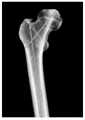

FIG. 2 is a femoral body surface projection image and an X-ray projection image according to an embodiment of the present application;

For example, see fig. 2 for a schematic representation of the position of the lesser trochanter of the femur.

Illustratively, referring to FIG. 2, the metaphysis width is 55 mm.

Illustratively, referring to figure 2, the isthmus is 12 mm in diameter.